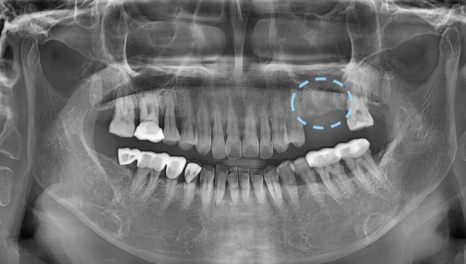

곡선의 구강을

직선 형태의 파노라마 상에서 확인하다 보니

실제 심어진 위치와 오차가 발생하기 때문인데요.

임플란트는 뼈에 식립하기 때문에

수술이 잘못되거나 재수술 하였을 때 다시 제거를 해야합니다.

그렇게 되면 뼈의 손상은 커질 수 밖에 없는데요.

임플란트 사이즈, 두께 , 신경관까지의 위치도 알 수 있습니다.

사전에 턱뼈의 두께, 폭 등 모두 고려하여

각도 및 임플란트 크기

전반적으로 파악

가장 이상적인 수술이 가능한 위치에 식립됩니다.